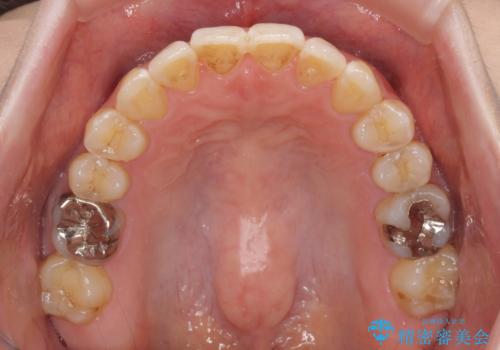

- 前歯のデコボコを治したいとのことで来院された患者様です。

上下顎ともに歯列全体の後方移動とIPR(歯と歯の間を削る)によってデコボコが解消するように設計し、インビザラインにより治療を行うこととしました。